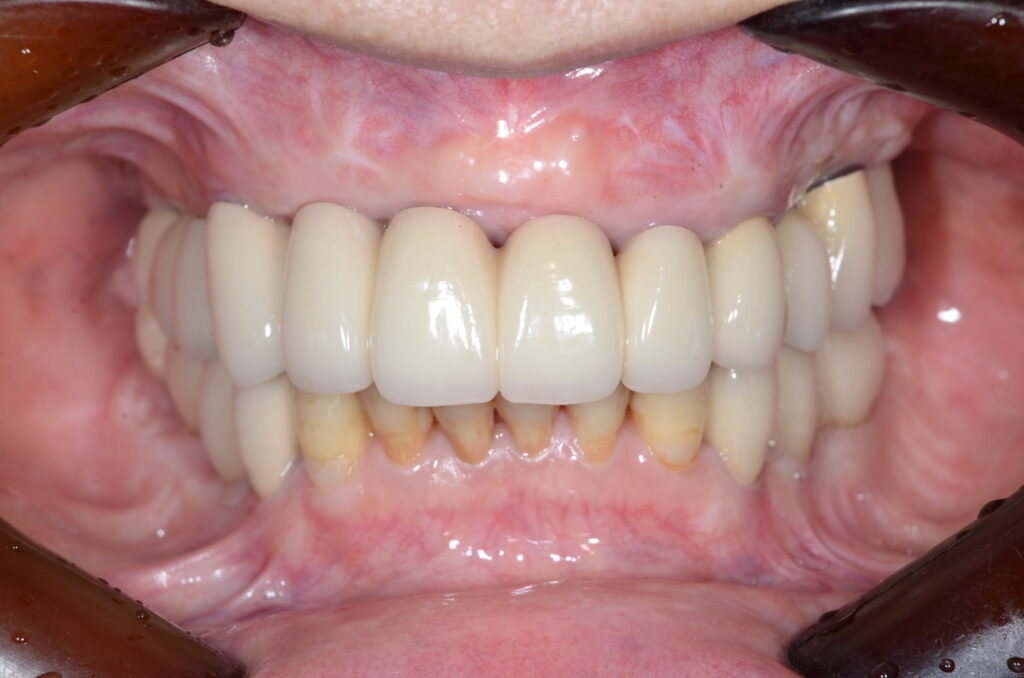

現在

3ヶ月に1度、定期検診を受診してくださっています

丁寧なセルフケアが行き届いているため、予後がとても安定しています

歯周病についても歯周ポケット数値や歯肉の状態も良い状態をキープされています

定期検診の際には、虫歯の有無や歯周病の具合だけでなく、被せ物に緩みがないか、噛み合わせのバランスが適切かどうかも併せて確認をしていきます